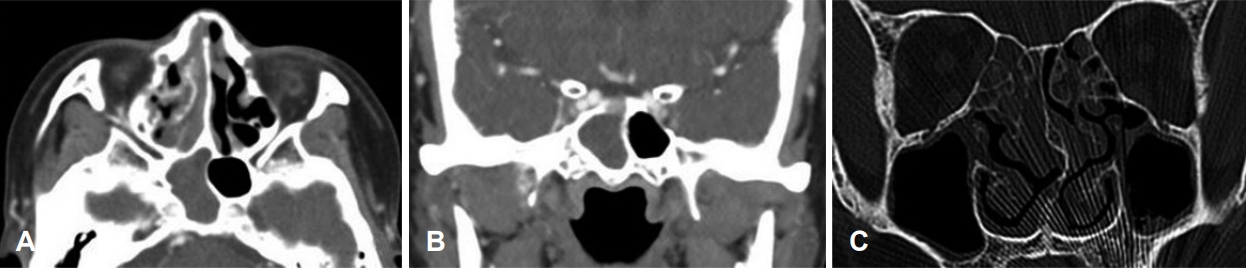

58세 여자 환자가 내원 2일 전부터 시작된 두통과 가벼운 비회전성 어지럼증으로 본원 신경과에 내원하였다. 환자는 기저 질환이 없이 건강하던 자로 두통은 간헐적으로 머리 전반적인 부위에서 발생한다고 하였고, 신경학적 검사상 이상소견은 보이지 않았다. 말초성 현훈 감별 위해 두부충동 검사, 두위충동 검사, 두위안진, 냉온교대 온도안진 검사(bithermal caloric test) 등을 시행하였으나 특이 소견은 관찰되지 않았다. 이에 추가 정밀 검사 및 보존적 치료를 위해 신경과로 입원하였다. 일반 혈액 검사에서 백혈구는 10.07×103/uL에 중성구 81%, 적혈구 침강속도는 86 mm/hour로 증가되었으나 그 외 검사상 다른 이상 소견은 보이지 않았다. 뇌 확산 자기공명영상(brain MR diffusion)을 촬영하였고, 허혈성 병변 및 뇌실질의 병변은 확인되지 않았으나, 우측 사골동과 접형동 부비동염 의심 소견이 확인되었다. 입원 2일째 환자가 갑작스러운 복시와 우측 안검하수를 호소하여 시행한 안과 검진상 시력, 안압 등은 정상이었고, 안구 운동 시 우안의 내전, 외전, 상전, 하전 제한과 안검하수가 관찰되었다(Fig. 1). 우측 사골동과 접형동 부비동염 및 우측 동안 및 외전 신경 마비 의심하에 부비동 전산화단층촬영(paranasal sinus CT, PNS CT) 및 후두와 자기공명영상(posterior fossa MRI)을 시행하였다. MRI에서 팽윤된 양측 해면정맥동과 주변 경막의 비후 소견이 관찰되었으며, 상기 소견은 우측이 더 심하였고 혈전 형성은 보이지 않았다(Fig. 2). PNS CT상 우측 전두동, 상악동, 사골동과 접형동의 연부조직음영이 있었으며, 좌측 상악동, 사골동과 접형동에도 일부 음영증가 소견이 보였고, 골결손은 보이지 않았다(Fig. 3). 환자는 코막힘, 후각 감퇴, 콧물, 재채기 등의 비증상은 호소하지 않았으나, 비강 검사상 좌측 비중격 만곡증 및 양측 비용 소견이 관찰되었다. 임상학적 양상과 영상 소견을 종합한 결과 급성 부비동염에 병발된 해면정맥동혈전염으로 인한 우측 동안 및 외전 신경마비로 의심되어 부비동 내시경 수술과 항생제와 스테로이드 정맥주사(ampicillin/sulbactam 1.5 g tid, cefotaxime 1 g tid, metronidazole 500 mg tid, dexamethasone 5 mg bid)를 진행할 것을 계획하였다. 입원 3일째, 전과 후 비중격 교정술과 양측 부비동 내시경술을 시행하였다. 전신마취하에 비중격 교정술 후 우측 전두동, 상악동, 사골동의 비용과 병변 점막을 제거하면서 자연공을 충분히 넓혔으며, 접형동 개구술을 통해 배농을 시행하였다(Fig. 4). 좌측 사골동, 상악동, 접형동도 비용과 병변 점막 제거 및 개방술을 진행하였다. 술 후 1일째, 두통, 어지럼증과 안검하수는 호전되었으나, 복시는 지속되는 양상이었다. 술 후 5일째에 안검하수 증상은 개선되었고, 우측 주시시 여전히 복시를 호소하였다. 술 후 7일째 퇴원하고 경구 항생제, 경구 스테로이드, 비강 스테로이드제(amoxicillin/clavulanate potassium 1 g bid, prednisolone 10 mg bid, fluticasone 5 mg qd)를 3주간 사용하였다. 추적 관찰하기 위해 촬영한 PNS CT상 양측 상악동, 사골동과 접형동의 부비동염 양상은 대부분 호전되었다(Fig. 5). 술 후 1개월째 안과 진료를 통해 복시가 개선된 것으로 확인되었고, 수술 2개월경 시행한 안과 검진상에서 외안근 기능이 모두 정상화된 것을 확인할 수 있었다(Fig. 6).

해면정맥동 혈전염의 진단을 위해서는 전산화단층촬영이 가장 중요하며 우선적으로 시행되어야 한다. 이를 통해 접형동의 함기화 정도 및 골미란 여부와 접형동 병변과의 관계성을 확인해 볼 수 있으며, 골미란 소견이 있거나, 시력 저하, 복시, 안검하수 등 뇌신경마비 소견이 보이는 경우 뇌 자기공명영상을 추가로 시행해야 한다[8,9]. 해면정맥동 혈전염의 자기공명영상 소견으로는 해면정맥동의 비대칭적 팽창과 혈전 형성을 시사하는 해면정맥동 내 불규칙한 다발성 충만 결손(filling defect), 해면정맥동 내 내경동맥(intracavernous internal carotid artery)의 현저한 내경 감소 및 해면정맥동 주위 경막의 조영증강 등이 있고, 상안정맥 확장이나 안구 돌출 양상도 보일 수도 있다[5,7,10]. 본 증례에서는 뇌 자기공명영상에서 양측 해면정맥동의 팽창 및 주변 경막의 조영 증강 소견을 보여 해면정맥동 병변을 의심해볼 수 있었으며, 충만 결손은 확인되지 않아 혈전은 뚜렷하게 생성되지 않았음을 확인하였다. 영상 소견에서는 양측 해면정맥동 혈전염이 확인되었지만, 환자는 우측에서만 안증상을 보였다. 해면정맥동 혈전염은 양측으로 교통되어 있어서, 원인 질환이 일측이라도 양측으로 금방 전파될 수 있다[7,11]. 본 증례에서는 우측 사골동염과 접형동염이 상대적으로 심하였기 때문에 안증상이 우측에서 먼저 확인되었고, 빠른 치료가 없었으면 좌측 안증상도 발생했을 가능성이 있다고 생각된다.